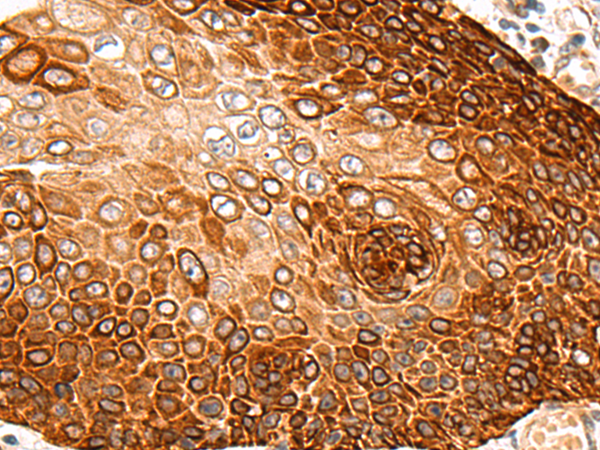

分类: 科研抗体货号: P08199别名:应用: IHC反应种属: Human